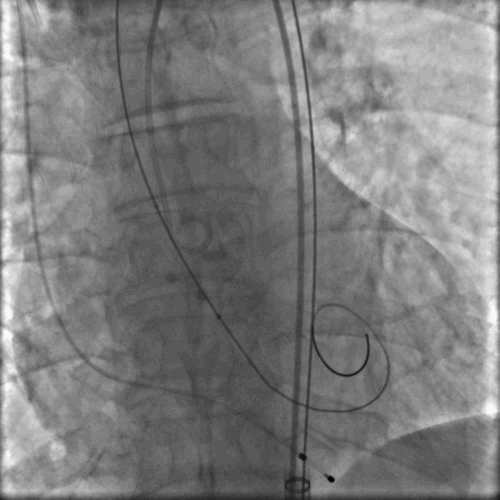

典型病例1

手术由首都医科大学附属北京安贞医院心内科周玉杰副院长、心外科张海波教授、心内科刘巍教授及其团队组成的TAVR心脏瓣膜团队共同完成。中国医学科学院阜外医院吴永健教授、四川大学华西医院冯沅教授、复旦大学附属中山医院潘文志教授等与会专家深度参与手术相关步骤的讨论和技术交流。